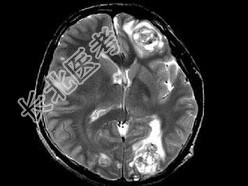

- 单项选择题男,22岁, 耳后见一直径约2cm黑痣,表现有溃烂, 近期增大明显,头痛1周, 伴咳嗽、胸闷,行头颅CT及MRI检查见颅内多发病灶, 最可能的诊断为 ( )

A、黑色素瘤脑转移